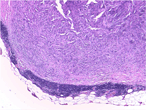

Diffuse vascular malformation of large intestine clinically and radiologically misdiagnosed as ulcerative colitis

Dilasma Ghartimagar and others

Journal of Surgical Case Reports, Volume 2017, Issue 2, February 2017, rjx016, https://doi.org/10.1093/jscr/rjx016